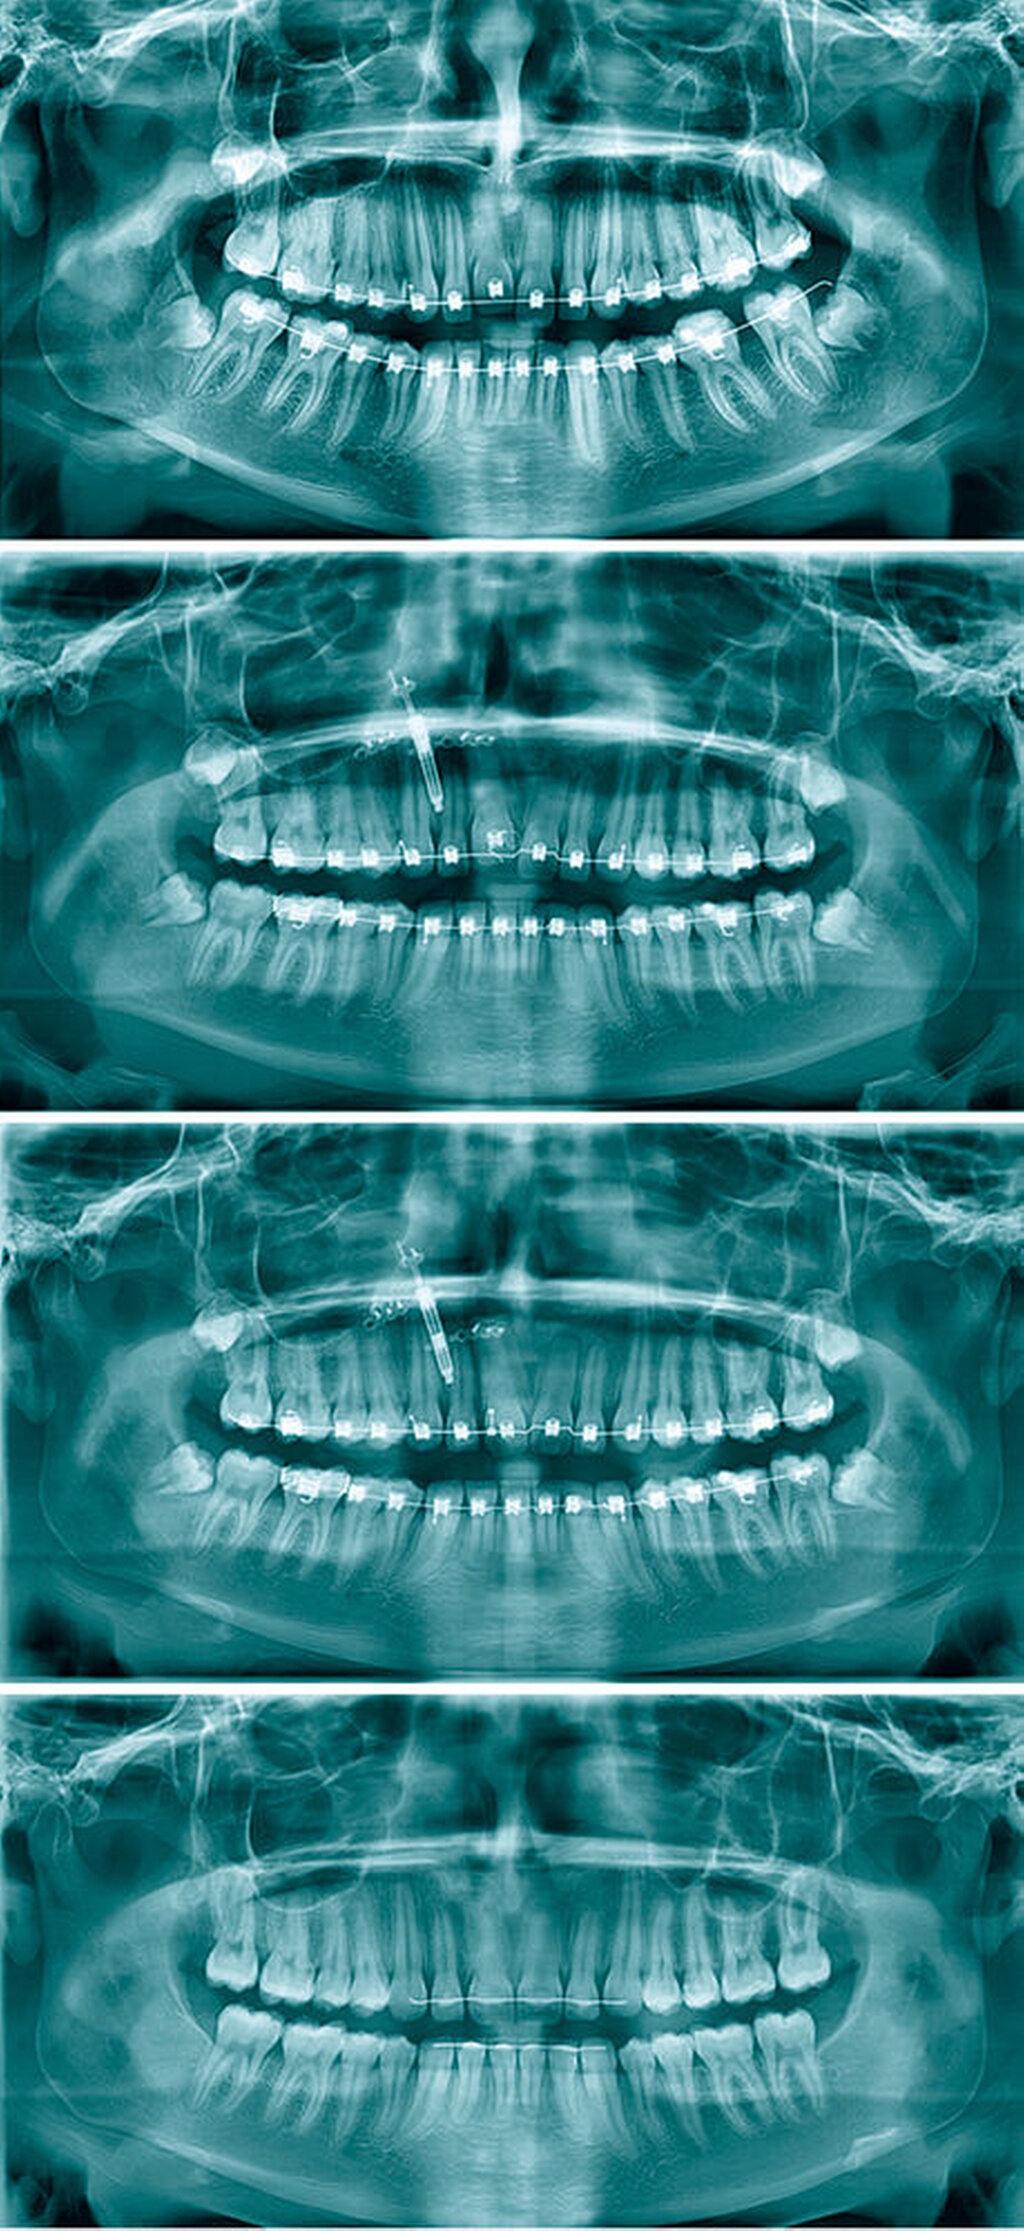

Vor dem kieferorthopädischen Behandlungsbeginn konnte eine Ankylose des Zahnes 11 klinisch und radiologisch weder sicher ausgeschlossen noch bestätigt werden. Die Patientin wurde nach differenzierter Befunderhebung und Diagnostik daher noch vor dem Beginn der Behandlung über die Möglichkeit der Ankylose des Zahnes 11 aufgeklärt und auf alle relevanten Therapiealternativen hingewiesen. Dann erfolgte die Behandlung mit einer festsitzenden Multibracketapparatur. Nach der Eingliederung fand zunächst die Nivellierung mittels thermoaktivierter Nitinol-Bögen statt. Unter engmaschiger Kontrolle der Nivellierung von 11 und insbesondere der Nachbarzähne 12 und 21 wurde klinisch die Diagnose einer Ankylose des Zahnes 11 gestellt. Der Zahn 11 wurde somit aus der Behandlung ausgenommen, zunächst wurden die restlichen Zähne sowie die Bisslage korrigiert.

Hierzu erfolgte die Vorstellung in der Medizinischen Hochschule Hannover. Klinisch fielen zum Zeitpunkt der Überweisung insbesondere die nun deutlich nach apikal abweichende Rot-Weiß-Grenze und die Unterentwicklung des Alveolarfortsatzes auf (Abbildung 2). Radiologisch zeigte sich ein am ehesten im Bereich des distalen Parodontalspalts ankylosierter Zahn 11 bei sonst regelgerechtem Befund. Unter Berücksichtigung des hohen Anspruchs der Patientin an die Ästhetik kamen prothetische oder implantatprothetische Lösungen primär nicht in Betracht. Es folgte die ausführliche Besprechung der Therapieoptionen und der damit einhergehenden Chancen und Risiken. Gemeinsam wurde der Entschluss zur Einzelzahnsegmentosteotomie mit Distraktorimplantation getroffen.

Nach Aufbringen von distalen Aufbissen zur Entlastung des Zahnes 11 sowie der schrittweisen Ligatur des Brackets 11 mittels Lassomechaniken an den Stahlbogen mit Hook-Konstruktionen zur Herstellung eines Hypomochlions konnte die Palatinalbewegung des Zahnes 11 suffizient antagonisiert werden. Nach Erreichen der designierten Endposition erfolgte eine sechswöchige Haltephase. Der Distraktor wurde in Allgemeinanästhesie explantiert und die noch in situ befindlichen Weisheitszähne durch Osteotomie entfernt. Postoperativ zeigte sich nach vollständiger Abheilung ein ausgezeichnetes Distraktionsergebnis. Die im Verlauf angefertigten Röntgenaufnahmen bestätigten das Ergebnis (Abbildung 5).